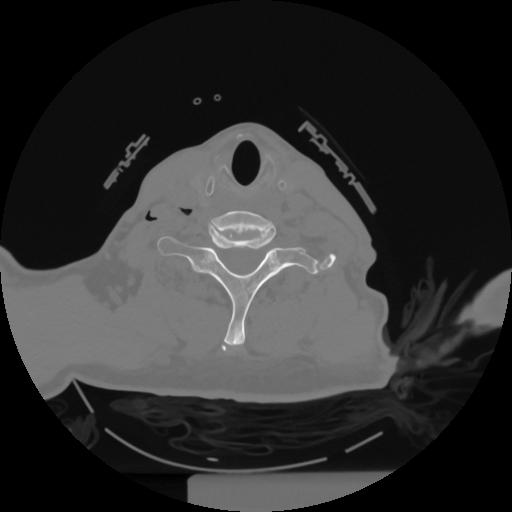

12 P.BLANDAS,,Vol,0.5,P.BLANDAS,,